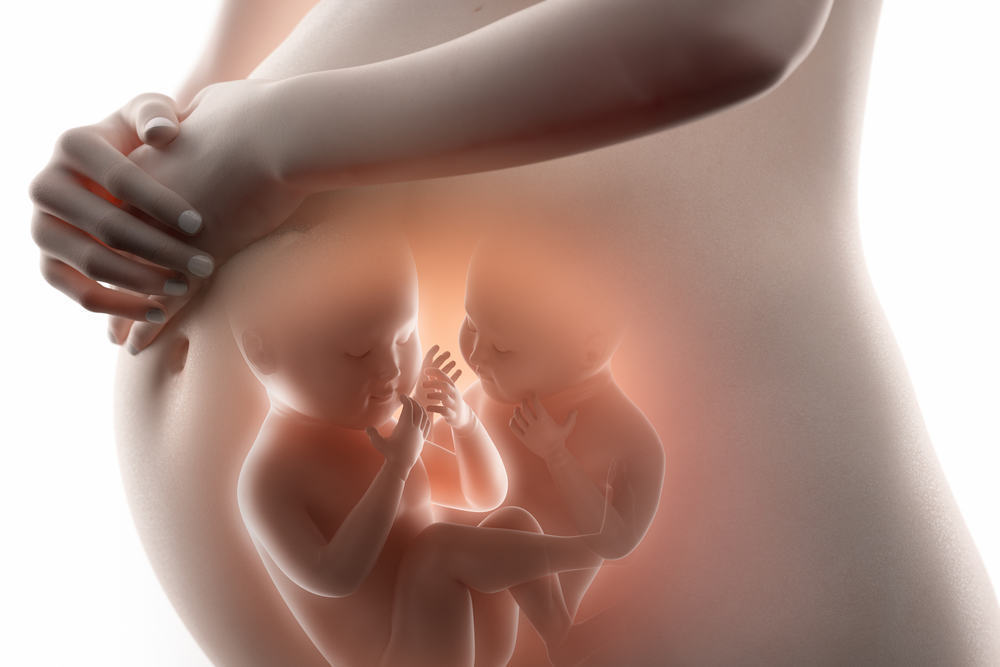

Загадочные образы животных в утробе матери

Раздел: Другие животные